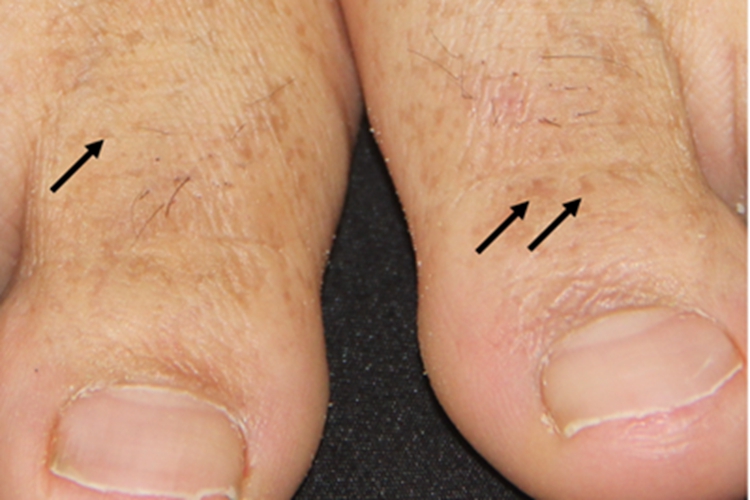

家族性进行性色素沉着症患者的皮肤损害可于脚趾处出现,呈色素沉着斑状改变,可呈褐色,随年龄增长加深,其间有点状或岛屿状正常皮肤区。